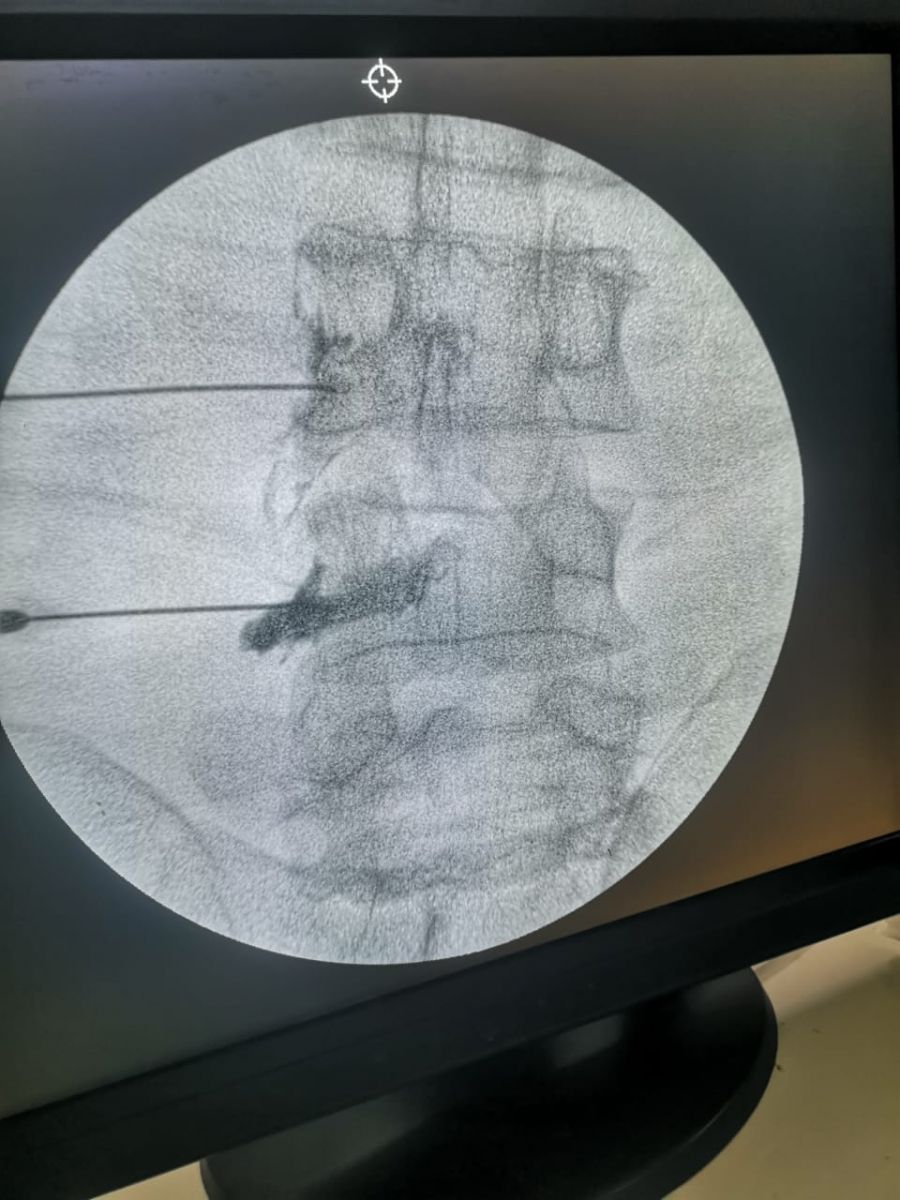

واستقبلت الوحدة السيدة الأولي والتي تبلغ من العمر ٥٨ عام، وكانت تعاني من آلام بالرقبة وخدر وتنميل بالطرف العلوي الأيسر، وآلام أسفل الظهر وعرق النسا بالساق اليمنى، والتهاب بمفاصل العمود الفقري، بسبب غضاريف معتلة متعددة المستويات بالفقرات القطنية والعجزية، مع رفضها للتدخل الجراحي، وتم إجراء لها حقن فوق الأم الجافية لجذور الأعصاب والقناة العصبية بالرقبة والفقرات القطنية والعجزية بمواد مضادة للإلتهاب، وإجراء تسليك للقناة العصبية بمواد مذيبة للإلتصاقات، وحقن مفصل الحوض الحرقفي المعتل، وتردد حراري نابض على جذور الأعصاب، وإجراء كي بالتردد الحراري على الأعصاب الناقلة للألم من المفاصل الخلفية للفقرات القطنية والعجزية، وتم خروج المريضة وتحسن الحالة بالمتابعة في العيادة، مع توجيهها لإجراء جلسات العلاج الطبيعي.

وحرصت الوحدة على استقبال مريض يبلغ من العمر ٥٥ عاما، يعاني من آلم أسفل الظهر وألم بالساقين نتيجة لضيق القناة العصبية بمنطقة الفقرات القطنية، وتم إجراء له حقن القناة العصبية بمواد